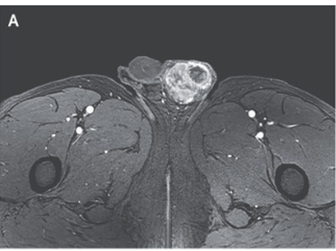

MRIでは不均一な協調を伴う分葉状の左精巣塊を認めた。